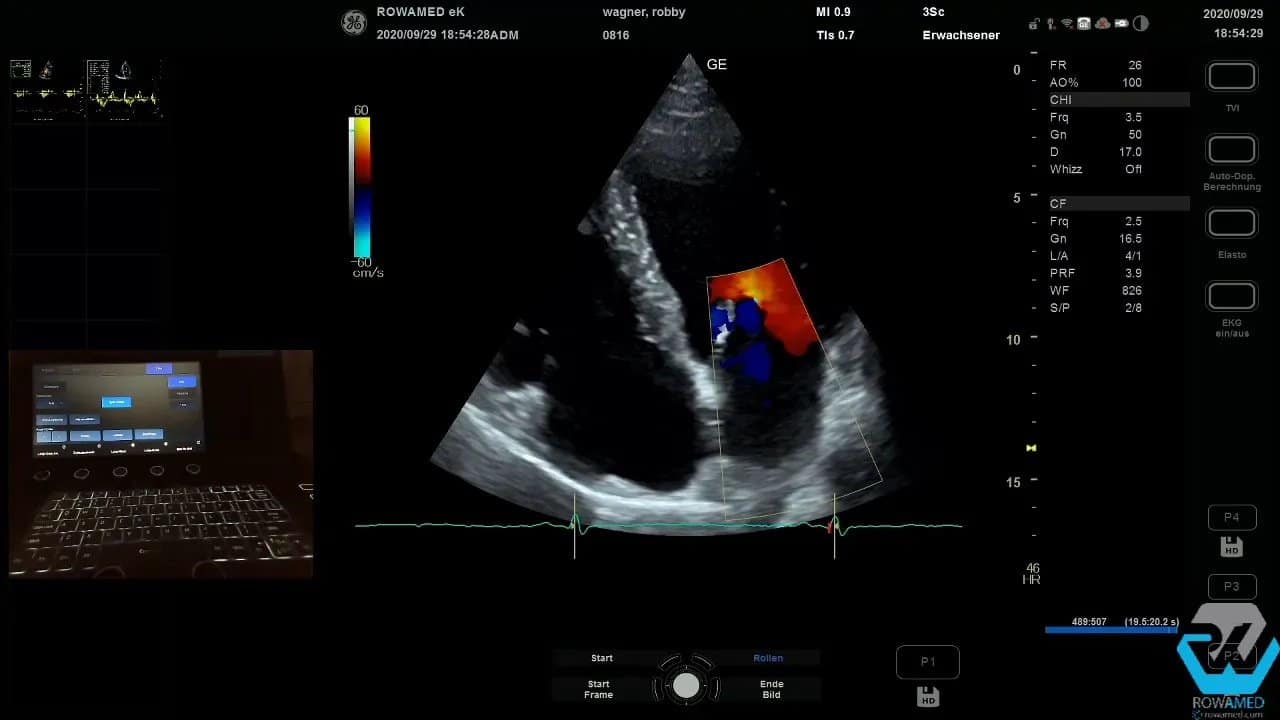

Wenn bereits eine bekannte Klappeninsuffizienz im Raum steht, schalten Sie jetzt den Farbdoppler dazu. Das ist in der Transthorakale Echokardiographie der schnellste Weg, um einen ersten funktionellen Eindruck zu bekommen.

Im Beispiel bestand der Verdacht auf eine Aortenklappeninsuffizienz. Im Farbdoppler zeigte sich jedoch keine relevante Aorteninsuffizienz. Stattdessen fiel eine kleine Mitralinsuffizienz auf. Auch das ist typisch: Der erste Verdacht bestätigt sich nicht immer, und manchmal findet man die eigentliche Auffälligkeit an anderer Stelle.

Wichtig bei der Farbdoppler-Beurteilung:

- Skalierung und Farbbereich passend einstellen

- auf Aliasing und technische Artefakte achten

- nicht nur auf die Jet-Länge schauen

- vor allem die Jet-Breite an der Durchtrittsebene berücksichtigen

Ein langer Jet wirkt schnell eindrucksvoll. Für die Schweregradbeurteilung ist aber entscheidend, wie breit die Regurgitation direkt an der Klappe ansetzt. Ein oben schmaler Jet kann trotz größerer Ausdehnung im Vorhof nur geringgradig sein.

Step 11: Klappeninsuffizienzen richtig einordnen

Bei der Mitralklappe zeigte sich ein relativ kräftig wirkender Jet, der an der Durchtrittsebene jedoch sehr schmal war. Das spricht für eine geringe bis allenfalls mittelgradige Mitralinsuffizienz. Genau an dieser Stelle passieren viele Fehleinschätzungen. Wer nur auf die Länge des Jets blickt, überschätzt leicht den Schweregrad.

Für die Standarduntersuchung reicht häufig die semiquantitative Beurteilung. Eine weitergehende Quantifizierung wäre möglich, würde aber über den Basiskatalog hinausgehen.

Noch wichtiger ist ein methodischer Grundsatz: Regurgitationen immer in mehreren Ebenen beurteilen. In nur einer Projektion können Sie Klappeninsuffizienzen deutlich unter- oder überschätzen. Deshalb wurde die Mitralinsuffizienz zusätzlich in einer zweiten und dritten Ebene kontrolliert. Überall zeigte sich derselbe Eindruck: ein schmaler Jet, nicht problematisch, vereinbar mit einer geringgradigen Insuffizienz.